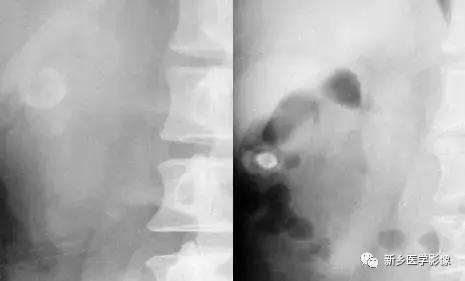

3、尿路结石

常见于尿路阳性结石,可以发生在尿路任何位置,如肾结石、输尿管结石及膀胱结石